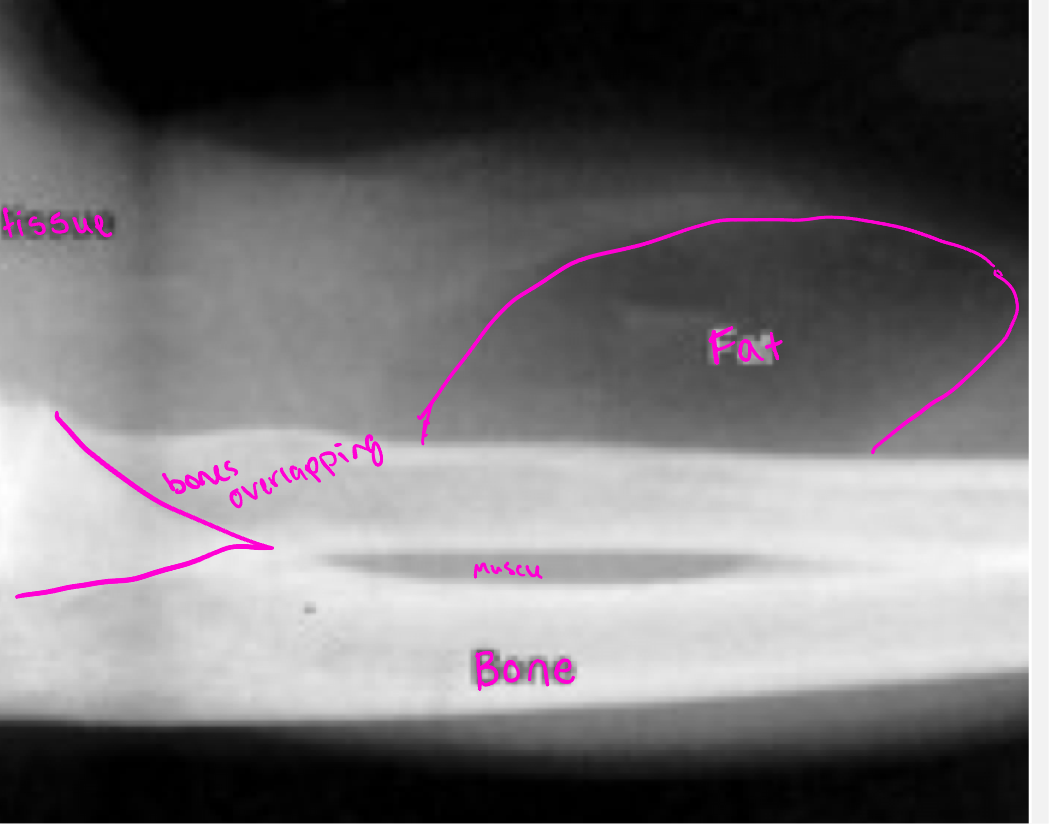

Summation density

reflects the density and thickness of intervening structures (two bones overlapping appear brighter than an individual bone)

Misleading appearance of overlapping structures

Poor soft tissue contrast resolution- ability to distinguish between differences in intensity in an image

Evaluation of bones- dense bone is surrounded by muscle and fat

Fractures, bone tumors